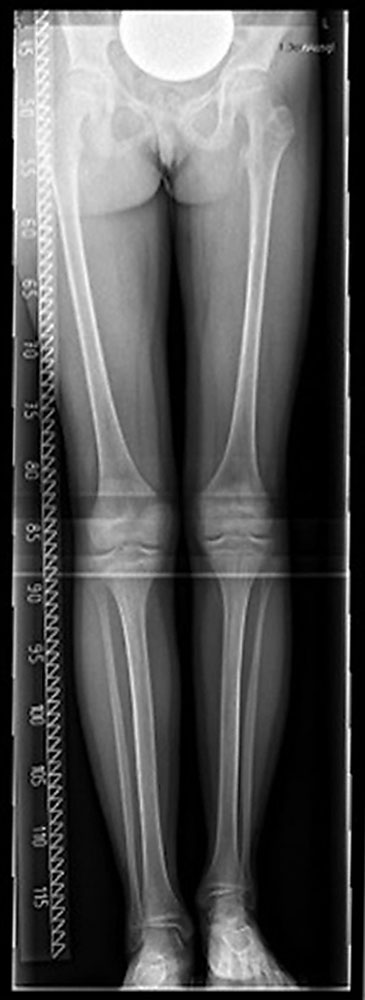

It is only in order to plan a surgical treatment that an X-ray needs to be taken as a so-called whole-leg axial X-ray. The exact length of the upper and lower leg bones (femur and tibia) can be measured on this X-ray and thus the location of the necessary therapy can be determined. At the same time, the bone age is often determined by comparison to a hand radiograph.